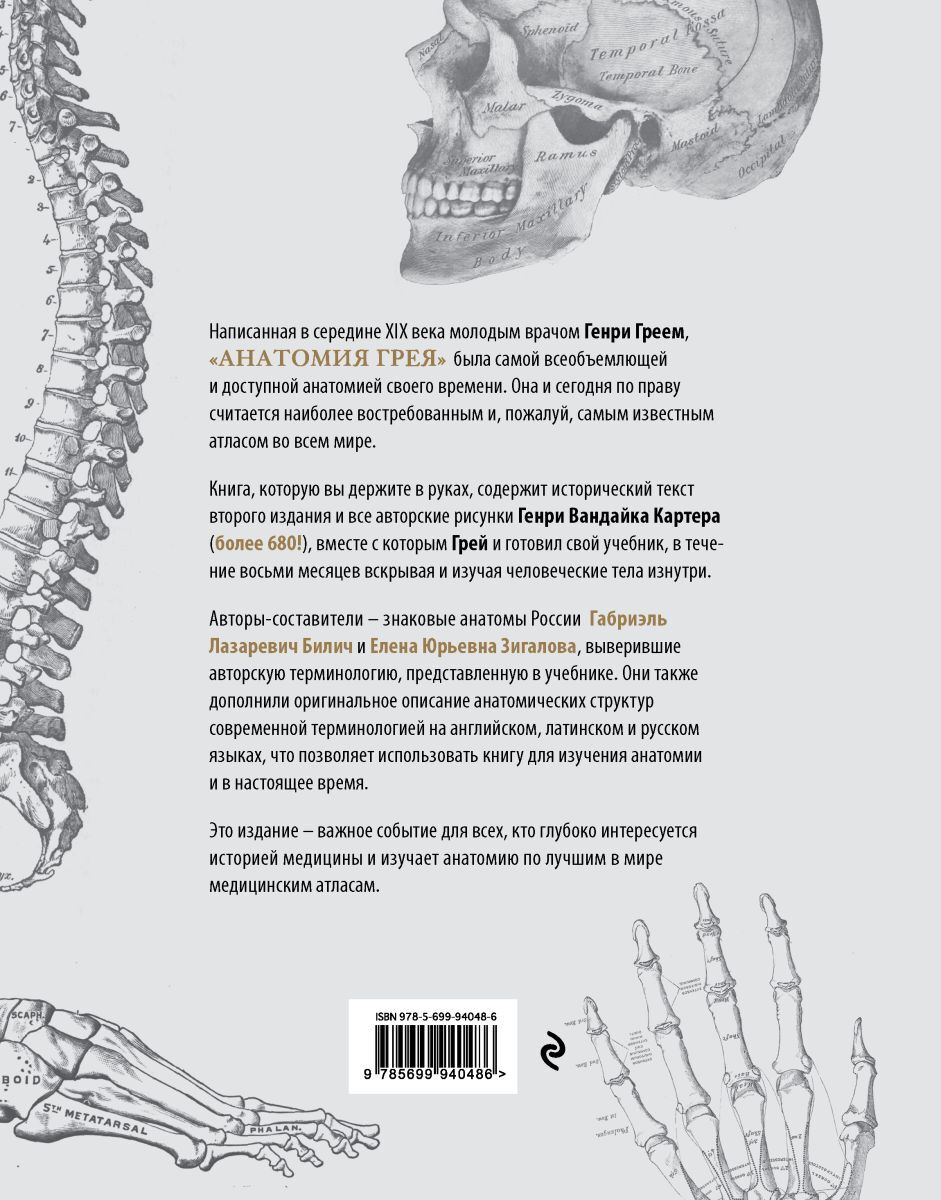

Написанная в 1850-х годах молодым врачом Генри Греем, "Анатомия Грея" была самой всеобъемлющей и доступной анатомией своего времени. Книга, которую вы держите в руках, содержит исторический текст второго издания и все авторские рисунки Генри Вандайка Карт

Написанная в 1850-х годах молодым врачом Генри Греем, "Анатомия Грея" была самой всеобъемлющей и доступной анатомией своего времени. Книга, которую вы держите в руках, содержит исторический текст второго издания и все авторские рисунки Генри Вандайка Карт

АвторБилич Габриэль Лазаревич, Зигалова Елена Юрьевна

ISBN978-5-699-94048-6